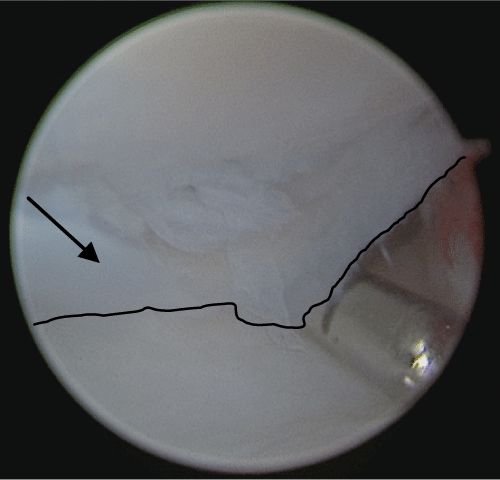

After conservative treatment with splinting, activity modification and oral anti-inflammatory analgesia, symptoms persisted, and a right wrist arthroscopy identified dorsal synovitis, extensive chondral detachment of the articular proximal surface of the lunate and triquetral chondromalacia (Figure 4, Figure 5 and Figure 6). A corticosteroid injection was deemed unsuitable pre-operatively with a diagnosis of AVN and no external signs of synovitis.

Figure 5: Right radiocarpal arthroscopy (3/4 and 6R portals): Lunate chondral flap (arrow and black line outlining flap edge) with lunate bone above and lunate fossa of distal radius below. View Figure 5